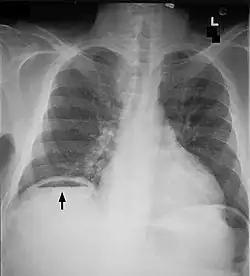

Un pneumopéritoine de faible volume est le plus souvent asymptomatique. Il est avant tout suspecté dans un contexte clinique. La radiographie (abdomen sans préparation (ASP) et/ou cliché debout de face, centré sur les coupoles diaphragmatiques) permet généralement de faire le diagnostic, le pneumopéritoine apparaissant comme un croissant radio transparent sous-diaphragmatique, uni ou bilatéral et de taille variable[1]. Cependant, un pneumopéritoine de faible abondance peut facilement passer inaperçu a la radiographie. C'est pourquoi la tomodensitométrie (ou scanner abdominal) est aujourd'hui considérée comme l'examen de référence pour son diagnostic[2]. La tomodensitométrie permet de rendre visible des volumes aussi faibles que 5 cm3 d'air ou de gaz.